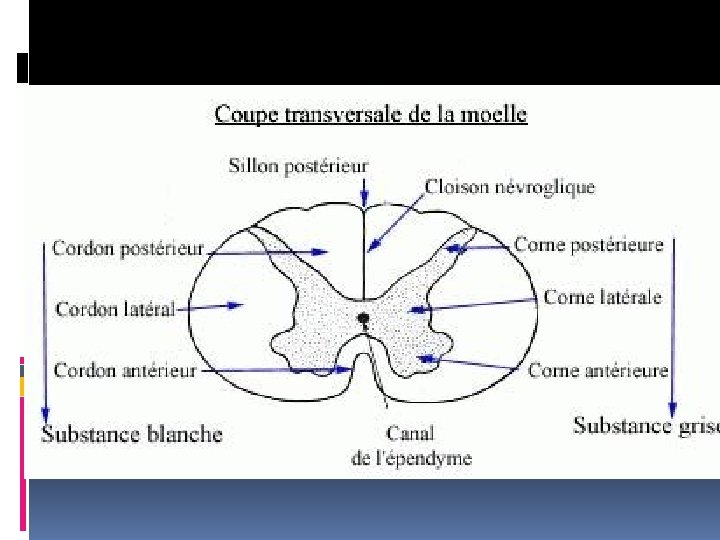

II. RAPPELS ANATOMIQUES